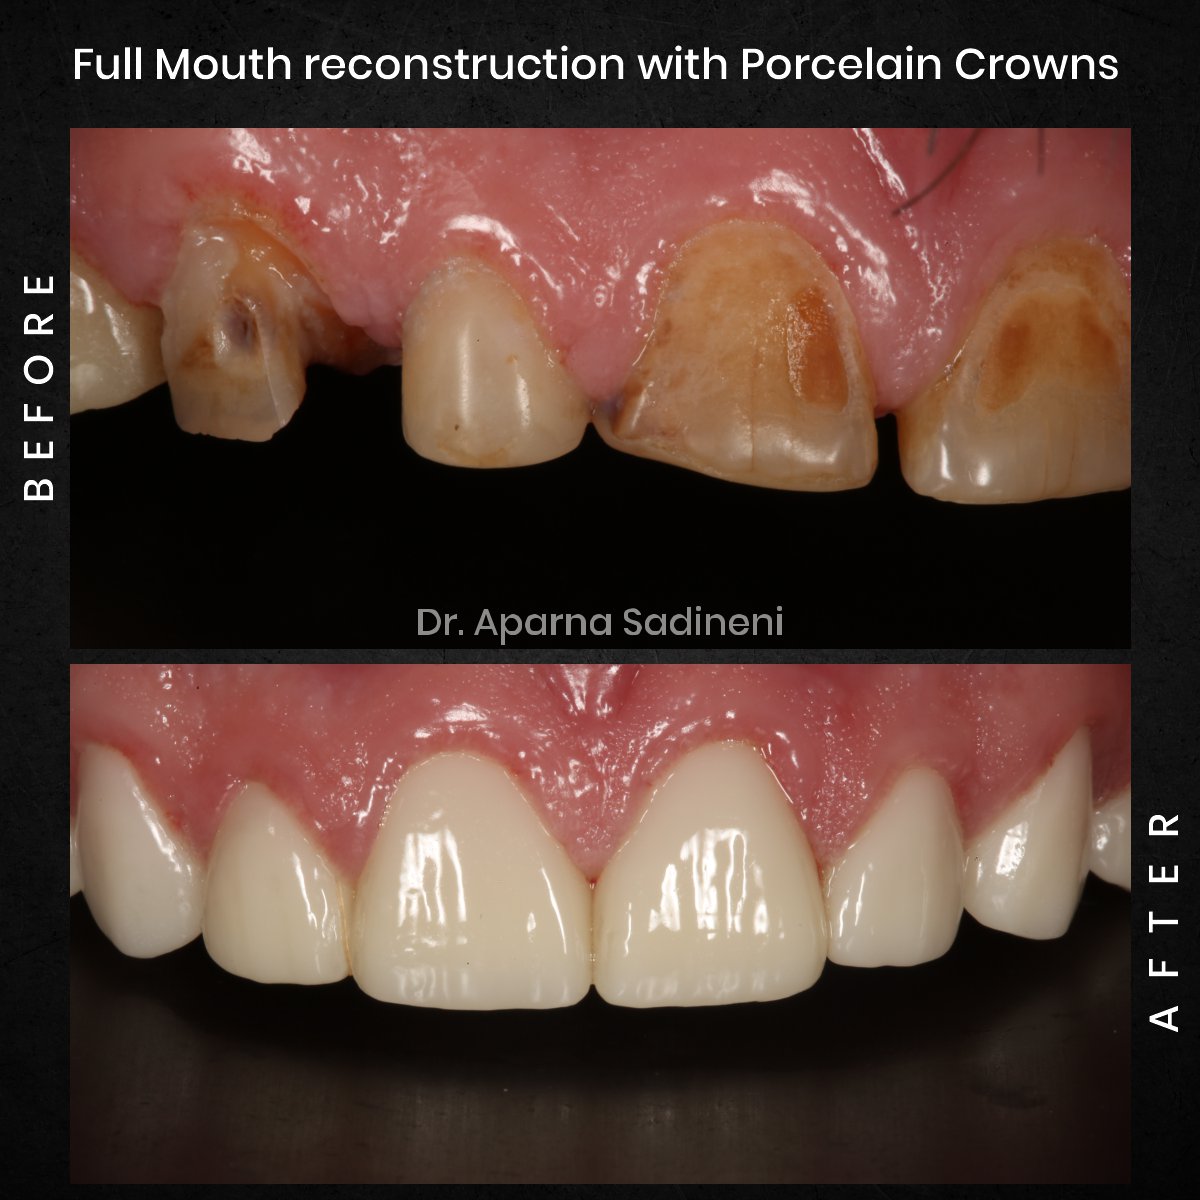

Joseph Crowns